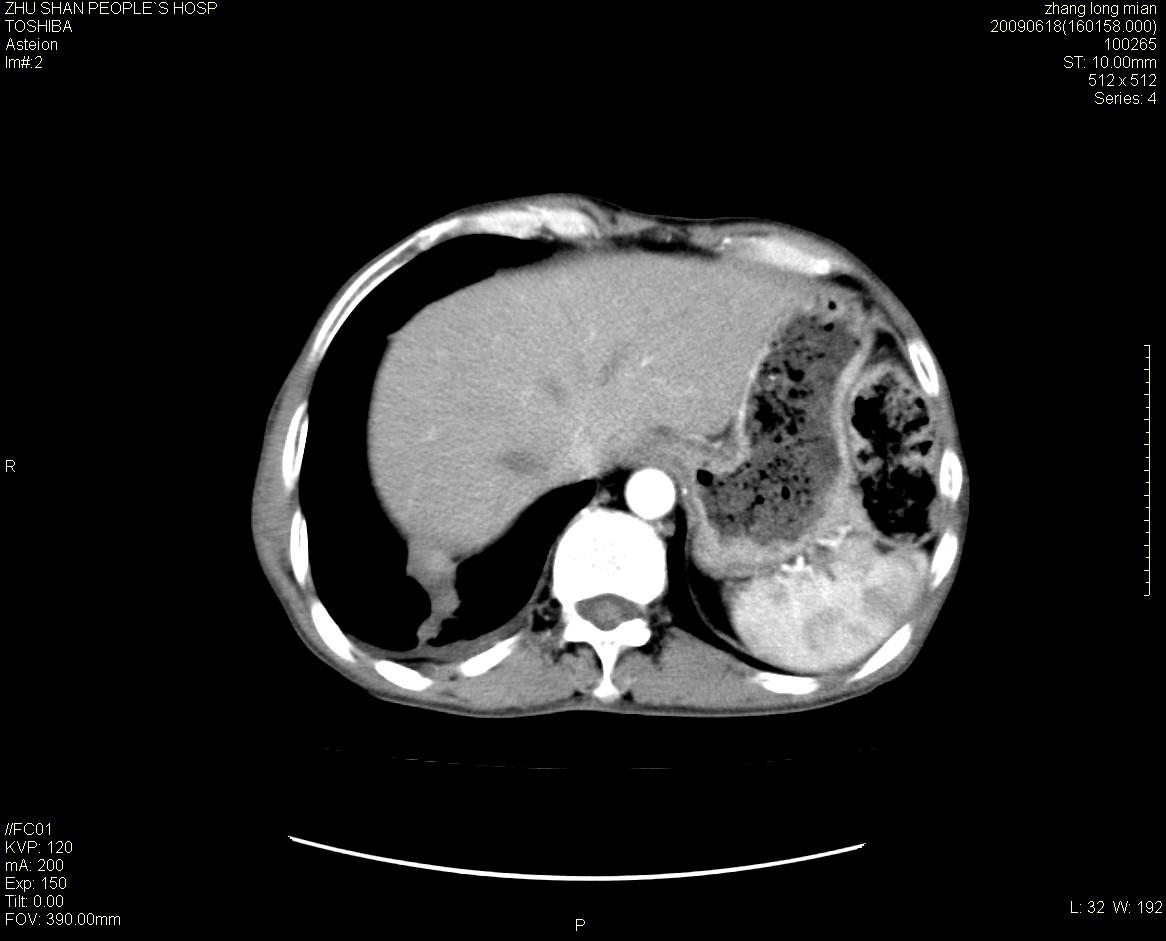

男性 65岁 胸片发现右下肺包块.诊断肺ca并纵隔转移没有问题吧!

右下肺见浅分叶状软组织块影,边缘有毛刺,其下部似见不完整偏心空洞影,邻近胸膜凹陷征,并胸腔积液。

增强见纵隔区气管隆突上下及左肺门区肿大淋巴结。左肺感染性病灶。